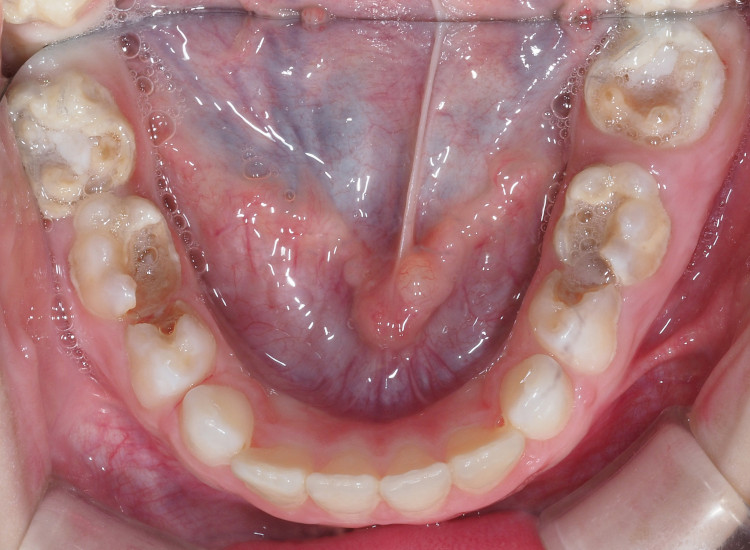

La carie precoce dell’infanzia si manifesta con delle macchie bianche o marroni che evolvono rapidamente in cavità sempre più estese, fino a creare un tessuto di consistenza molle. Queste aree di demineralizzazione coinvolgono prima i dentini frontali superiori, e possono estendersi anche ai molaretti da latte nel caso in cui non si intervenga in modo tempestivo.

Poiché la carie è solo una delle possibili cause dei denti neri nei bambini, se riscontri delle pigmentazioni anomale sui denti di tuo figlio ti consigliamo di fissare una visita di controllo dal dentista per identificare l’origine del problema.